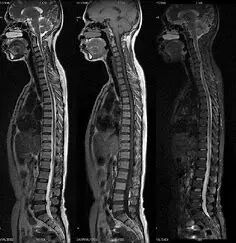

CT即计算机断层扫描,计算机断层扫描是一种非侵入性的医学成像技术,CT扫描的基本原理是旋转X射线源和对应的检测器围绕患者身体旋转,同时采集穿过人体不同部位的X射线数据。由于X射线在人体组织中的吸收率不同,因此在探测器上形成的信号强度也会有所不同。这些数据通过数学算法进行重建,生成一系列的二维切片图像。这些切片图像可以进一步堆叠和渲染,形成三维模型,从而提供更详细的解剖结构信息。

CT技术能够提供比传统X射线更清晰、更详细的图像,尤其是在观察骨骼、血管和内脏器官时。因此,在临床上,CT广泛用于诊断各种疾病,包括但不限于癌症、心脏病、中风、肺病和腹部疾病。对于慢性病,如肝病和肾病,CT也可以用来监测疾病的进展和治疗效果。